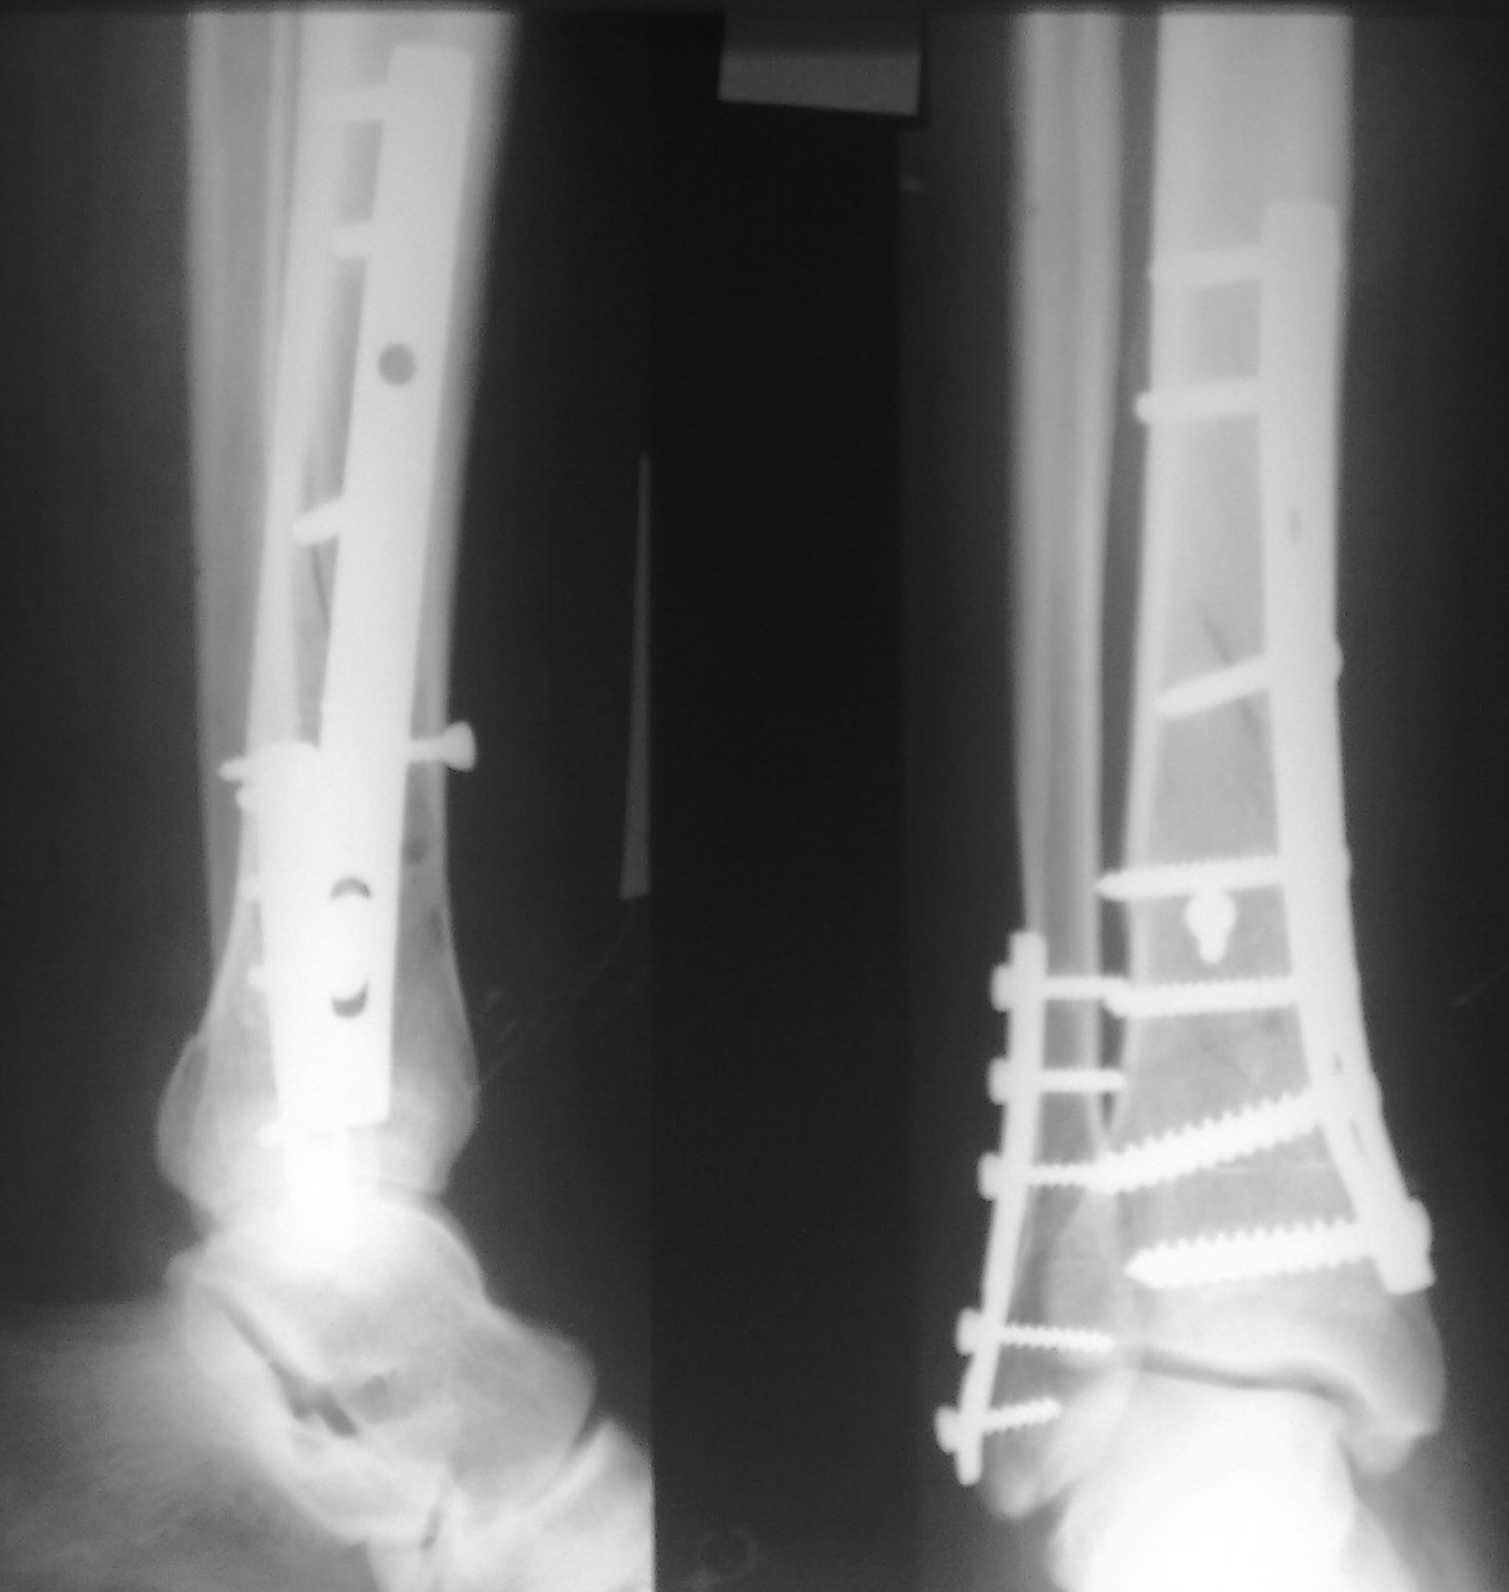

Спасибо за советы. Выполнен МОС обоих костей голени

По представленным послеоперационным снимкам создаётся впечатление сохраняющегося подвывиха + итраоперационно обнаруженный разрыв межкостной мембраны.

Извините за некачественные снимки и неправильную укладку в прямой проэкции. Подвывих рентгенологически не определяется. Кроме этого, после МОС малоберцовой кости интраоперационно однозубым крючком проверена стабильность синдесмоза - он стабилен. Кроме этого, интраоперационно проверена стабильность стопы в голеностопе - люфта ее при боковых отклонениях не определяется, также визуально при этом приеме отклонения малоберцовой кости кнаружи в ДМС не определяется. В дополнение к этому (у ассистента были сомнения) был сделан доступ к межберцовой связке и ее визуальный осмотр- она оказалась целой. При данных обстоятельствах позиционный винт мы не вводим.

Показания для остеосинтеза малоберцовой кости и наружной лодыжки при переломах голени и пилона известны и продолжают обсуждаться, литературу найти можно. Не вдавясь в подробности - в данном конкретном случае остеосинтез наружной лодыжки был желателен для ранней безболезненой реабилитации голеностопного сустава. Надобности в позиционном винте не было и быть не могло. Хочется только надеяться, что проведённая операция была достаточно доброжелательной к мягким тканям, хотя определённые детали послеоперационных Рентгенограмм могут косвенно свидетельствуют об обратном... Так же, как и достигнутая репозиция. Но это не входит в рамки обсуждения, насколько я понимаю. С уважением, Волна